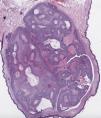

HistopatologíaSe realiza exéresis completa de la lesión, observándose en el estudio anatomopatológico una neoformación polipoide, no encapsulada (fig. 2), compuesta por nódulos tumorales localizados en dermis, separados entre sí por tractos fibrosos. Dichos nódulos están formados por 2 tipos de células: unas de forma redondeada y citoplasma claro, que presentan tinción PAS positiva (fig. 3), y otras poliédricas, de núcleos redondeados y citoplasma levemente basófilo. No se aprecian imágenes de mitosis ni invasión angiolinfática o perineural. Se demuestran quistes de contenido eosinófilo homogéneo, revestidos de una hilera de células de epitelio cuboidal, sin evidencia de secreción por decapitación.